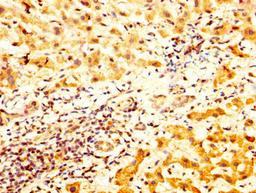

IHC image of CSB-PA023320LA01HU diluted at 1:800 and staining in paraffin-embedded human liver cancer performed on a Leica BondTM system. After dewaxing and hydration, antigen retrieval was mediated by high pressure in a citrate buffer (pH 6.0). Section was blocked with 10% normal goat serum 30min at RT. Then primary antibody (1% BSA) was incubated at 4°C overnight. The primary is detected by a biotinylated secondary antibody and visualized using an HRP conjugated SP system.